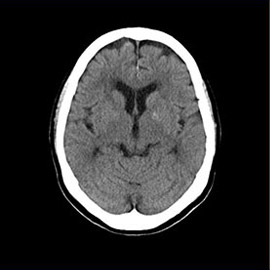

80列マルチスライスCT 検査 画像例

80列マルチスライスCTで撮影した画像

頭部